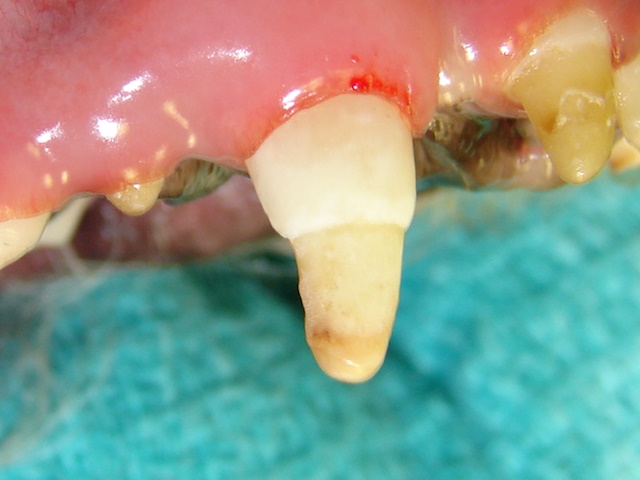

Enamel hypoplasia affecting nearly half of the canine tooth crown away from the gumline.

A dentin bonding agent is being applied to the exposed dentin to seal off the dentinal tubules.